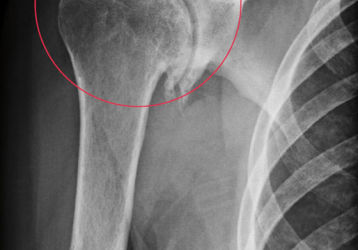

Симптомы и лечение остеохондромы бедренной кости, меры профилактики

Основные причины и симптомы остеохондромы бедренной кости: стадии болезни, возможные осложнения, методы диагностики и лечения, профилактические меры.